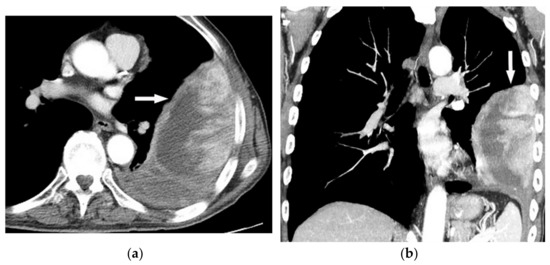

8.2. Tuberculosis Spondylodiskitis

Tuberculosis spondylodiskitis has a more gradual and chronic clinical course, which leads to multi-level involvement and paravertebral cold abscess formation with well-circumscribed thin wall. Subligamentous spread of infection to adjacent vertebral levels, relative preservation of intervertebral disk, and kyphotic angulation (gibbous deformity) are other imaging findings. CT scan is more sensitive in delineating calcification within paravertebral cold abscess, end plate erosion, and bony fragment visualization (Figure 13) [39,42].

Figure 13.

A 65-year-old man with fever, weight loss, and night sweeting. The non-contrast-enhanced CT (bone window) in axial plane (a) shows paraspinal soft tissue mass with erosion of right lateral aspect of adjacent vertebral body. Sagittal T2W image of another patient with the same pathology (b) shows hypersignal intensity within T8-T9 vertebral bodies with also intervertebral disc destruction and narrowing of spinal canal pushing the spinal cord posteriorly. Axial T1WFS + C (c) identified the enhancing paraspinal mass with peripheral rim enhancement (arrow) in its left posteromedial side, which is suggestive of abscess formation. Culture of aspirated pus under guide of CT was compatible with tuberculosis infection.